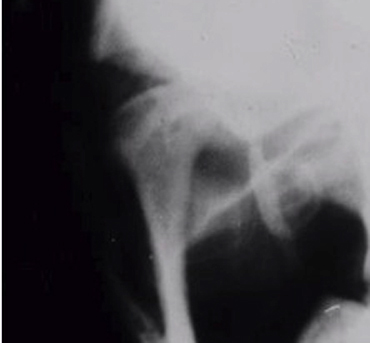

This is a modified anterior-posterior projection that produces an image that is perpendicular to the long axis of the condyle. It is taken with the mouth wide open which positions the condyle at the height of the tubercle to avoid superimposition of the condyle onto the base of the skull while simultaneously allowing the x-ray beam to be tangent to the inferior surface of the eminence and the superior surface of the condyle. This view is useful in trauma patients for identifying fractures of the condylar neck that might not show up on a panoramic image.